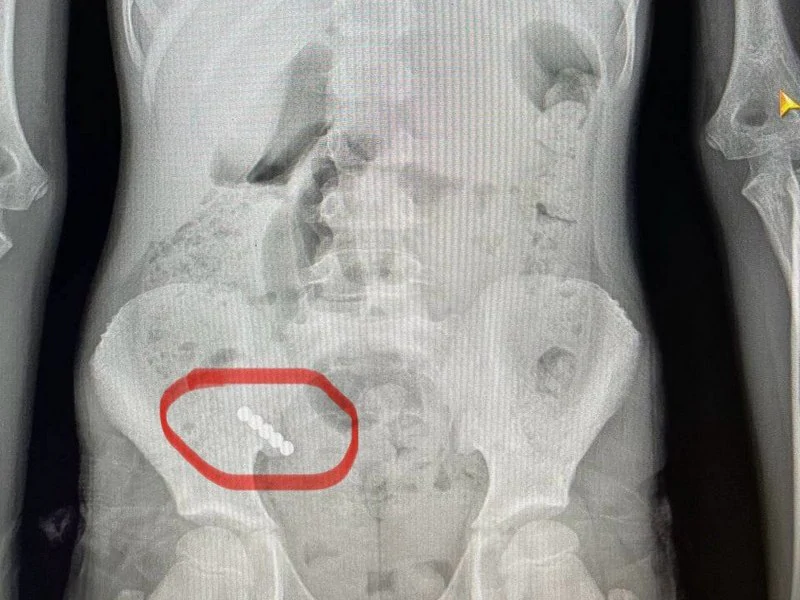

У Волинському обласному медоб'єднанні захисту материнства і дитинства врятували 9-річну дитину, яка проковтнула чотири магніти.  Про це повідомили на фейсбук-сторінці медичного закладу. Дитину до медзакладу доправила бригада екстреної медичної допомоги з діагнозом «гострий апендицит». «Водночас, — розповідає хірург ...